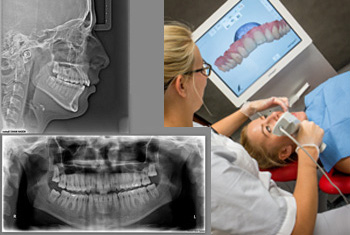

The first visit – preparing medical documentation During this appointment the dental hygienist performs a photo session of face and occlusion and also scans the jaws in 3D technology (instead of the traditional impressions)

She also makes a set of digital images and X-rays (pantomograms and cephalograms).